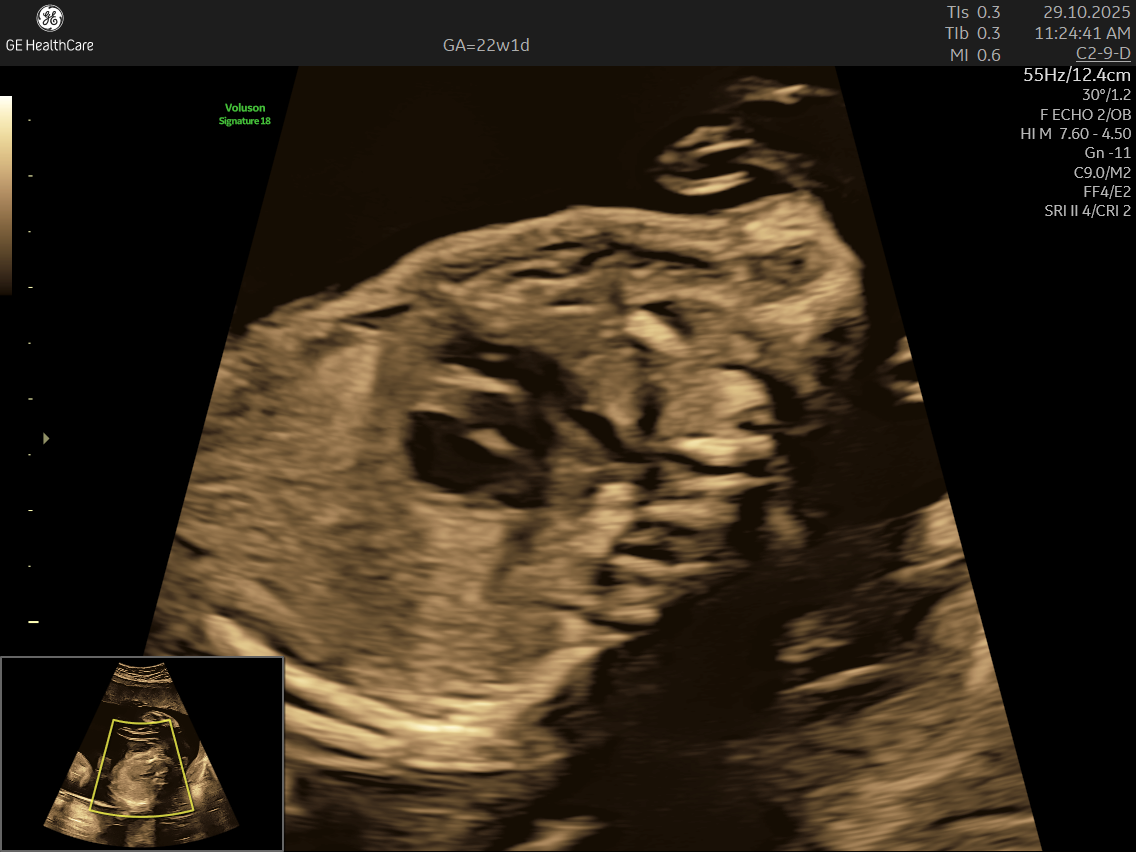

Fetal echocardiography is a valuabe early screening tool for Fetal Heart Defects. It is a specialized ultrasound scan that closely examines your baby’s heart while still in the womb. Unlike standard pregnancy scans, this test focuses on evaluating the structure, function, and rhythm of the fetal heart—providing incredibly detailed insights that help detect and diagnose congenital heart defects (CHDs) and other abnormalities early.

- Focus on the Heart: This scan is dedicated solely to assessing your baby’s heart—its structure, blood flow, and rhythm—offering a far deeper evaluation than standard ultrasounds.

- Specialized Equipment and Expertise: Performed with high-resolution machines and by specialist doctors, fetal echocardiography pinpoints tiny structural or functional abnormalities that conventional scans may miss—helping ensure early, accurate diagnosis and informed planning.

- Using the advanced GE Voluson S10 ultrasound machine—renowned for its superior imaging clarity, 4D real-time visualization, and automated analysis tools that significantly increase diagnostic accuracy and reduce the chances of missing subtle heart defects.

- Its a specialized ultrasound done between 18–24 weeks of Gestational Age that evaluates the structure, function, and rhythm of a baby’s heart while still in the womb. This scan uses high-frequency sound waves to create detailed images of the fetal heart, aiding in the detection of congenital heart defects (CHDs) and other abnormalities.